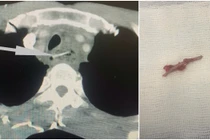

Nuốt hoặc hóc các dị vật như tăm tre, các loại xương, vỉ thuốc… là những tai nạn nguy hiểm có thể gây thủng đường tiêu hóa dẫn tới nhiễm trùng nghiêm trọng.

Các dị vật như xương cá, gà, lợn… thường sắc nhọn, dễ gây chảy máu, thủng thực quản, viêm, áp xe trung thất. Nếu phát hiện muộn, quá trình điều trị sẽ trở nên phức tạp và có thể đe dọa tính mạng.